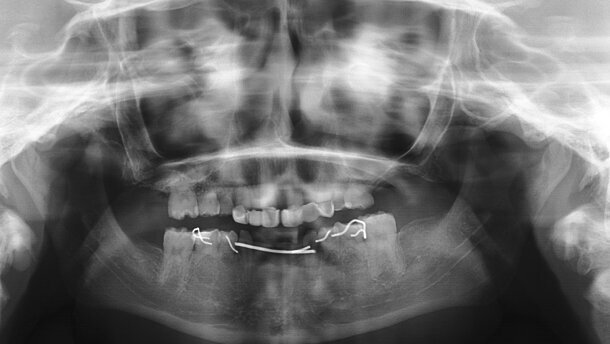

Niña de 15 años de edad, diagnosticada de síndrome de Johanson-Blizzard, que presentaba oligodoncia en la dentición temporal y permanente acude a la clínica para rehabilitación con implantes dentales. Era portadora de una prótesis fija maxilar ferulizada a sus dientes remanentes y una prótesis removible mandibular para reponer los dientes ausentes (figura 1 y figura 2). Se realizó una consulta interdisciplinar y una exploración clínica extraoral e intraoral, registros fotográficos, cefalometría lateral y una ortopantomografía (figura 3). Se montaron los modelos en un articulador semiajustable Whip-Mix 3000® (Whip-Mix Corporation, Louisville, USA) y se realizó un encerado diagnóstico para evaluar los parámetros estéticos y la relación de los dientes con el reborde alveolar (perfiles de emergencia). Se preparó una guía quirúrgica y se tomó un registro de oclusión céntrica en cera.

Se realizaron radiografías panorámicas después de la cirugía (digital ortopantomografía OP100, Instrumentarium Imaging, Tuusula, Finlandia) y Se prescribió amoxicilina + ácido clavulánico (875/125mg, 3 veces al día, 7 días), ibuprofeno (600 mg, 3 veces al día, 3 días) y enjuagues de clorhexidina al 0,12 %.

Las prótesis fueron atornilladas a las 24 horas, con tornillos cortos de prótesis y con un torque de 15 N-cm (figura 9). Se comprobó la oclusión (máxima intercuspidación, lateralidades y protusión) para ajustar una oclusión mutuamente protegida con función de grupo. La adaptación marginal de la restauración se controló con una ortopantomografía (figura 10).

La prótesis definitiva se empezó a confeccionar a partir de las 8 semanas de la colocación de los implantes. A los 3 años de la carga se realizó un control clínico y radiográfico (figura 10) (figura 11).

Las imágenes radiográficas panorámicas fueron calibradas con CliniView® (Version 5.1 program, Instrumentarium Imaging, Tuusula, Finlandia). Para realizar las mediciones, se determinaron dos puntos de referencia en la unión entre el implante y la restauración protésica, uno en mesial y otro en distal. Estos puntos son visibles y localizables en las radiografías panorámicas. Se trazó una recta que unía los dos puntos de referencia, considerando este eje como altura 0. Para determinar la pérdida ósea, una línea perpendicular fue trazada en mesial y distal del implante, desde ese eje al contacto con el hueso más coronal. La diferencia entre los valores encontrados en las dos mediciones (colocación de la prótesis y al año de la carga) fue usada para calcular la pérdida ósea en mesial y distal del implante, tomando la mayor de las dos como valor de referencia. Se encontró una pérdida ósea media de 0,76 ± 0,23 en los implantes inmediatos.